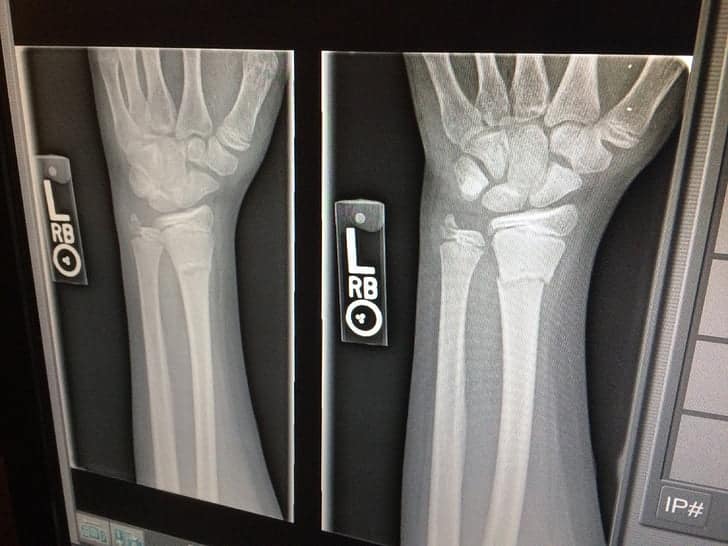

On the other hand, defendants argued that the child’s injury was caused by a rare condition known as acute subcutaneous lymphedema compression neuropathy and they met the applicable standards of care of each stage in treatment. Defendants presented x-ray imaging that showed unusual fluid collection in the child’s arm unrelated to the wrap, which they maintained was the ultimate cause of the child’s injuries.